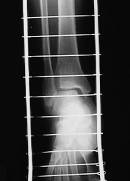

X線所見:正面像において腓骨下端部の骨折が認められ、中枢骨片の内側への転位が認められた。側面像において中枢骨片は前下方、末梢骨片は外後上方の骨片への転位が認められた。

【スライド4】

このスライドがその写真です。